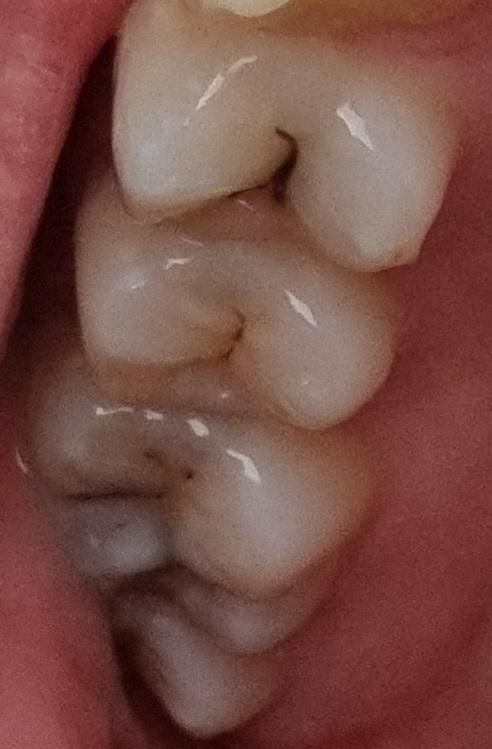

내일 치과 방문 예정인데 미리 생각을 해두고 싶어서요. 위의 사진이 약 1년 반 전의 치아 상태, 아래가 방금 찍은 사진입니다 위에서 3번째 이는 신경치료하기로 했고, 나머지 두 개는 지켜보고 아프면 충치치료 하자고 하셨는데... 사진 비교했을 때 진행이 많이 된 편일까요

진행이 많이 된것처럼 보이지 않지만 해당 정도의 충치라면 치료를 하는 것이 맞아 보입니다. 충치가 상당히 진행되었을 가능성이 매우 높아 보입니다. 다만 정확히 진행 정도를 알기 위해서는 x-ray 등의 촬영이 필요합니다. 따라서 가까운 치과 방문 후 x-ray 촬영을 권해드립니다.

진행이 되고 있는 것으로 보입니다. 치아를 직접 검사해봐야겠으나 치료가 필요해보입니다.

어금니쪽 충치는 많이 진행된거 같습니다 육안상으로는 판단하기가 어렵고 치과에 가셔서 엑스레이를 찍어봐야 정확히 알수 잇을것같습니다.

사진으로는 정확한 확인이 어려워 보입니다. 충치가 전반적으로 진행이 되고 있는 것으로 보입니다. 충치가 진행되고 있다면 빠르게 치료를 하는 것이 더 좋을 수 있습니다.

사진으로만 보기에는 정지우식으로 보이고 맨 위

치아는 침착물이 조금 많아서 긁어내고 방사선 사진을 찍어봐야 정확하게 알 수 있을 것 같습니다만 평소에 통증이 없었다면 크게 문제가 없을 것으로 보입니다.

셋다 충치는 진행중인 것으로 보입니다 이정도면 정지충치의 상태는 아니기 때문에 충치치료, 신경치료 늦지 않게 진행하는 것을 추천드립니다